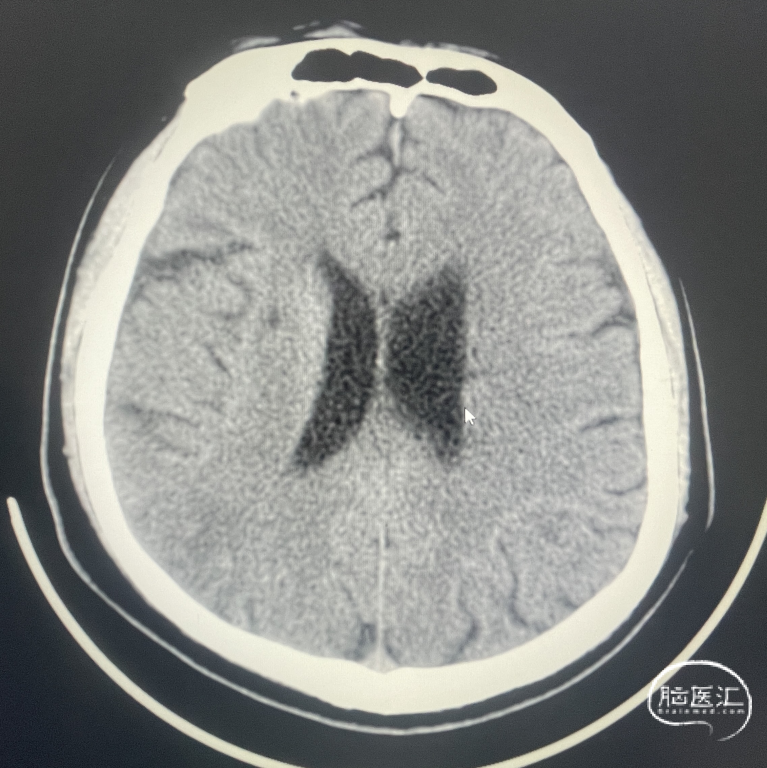

辅助检查:CT见右侧基底节区及右顶叶低密度病灶。

术后CT:术后即刻CT,以及术后24h CT。